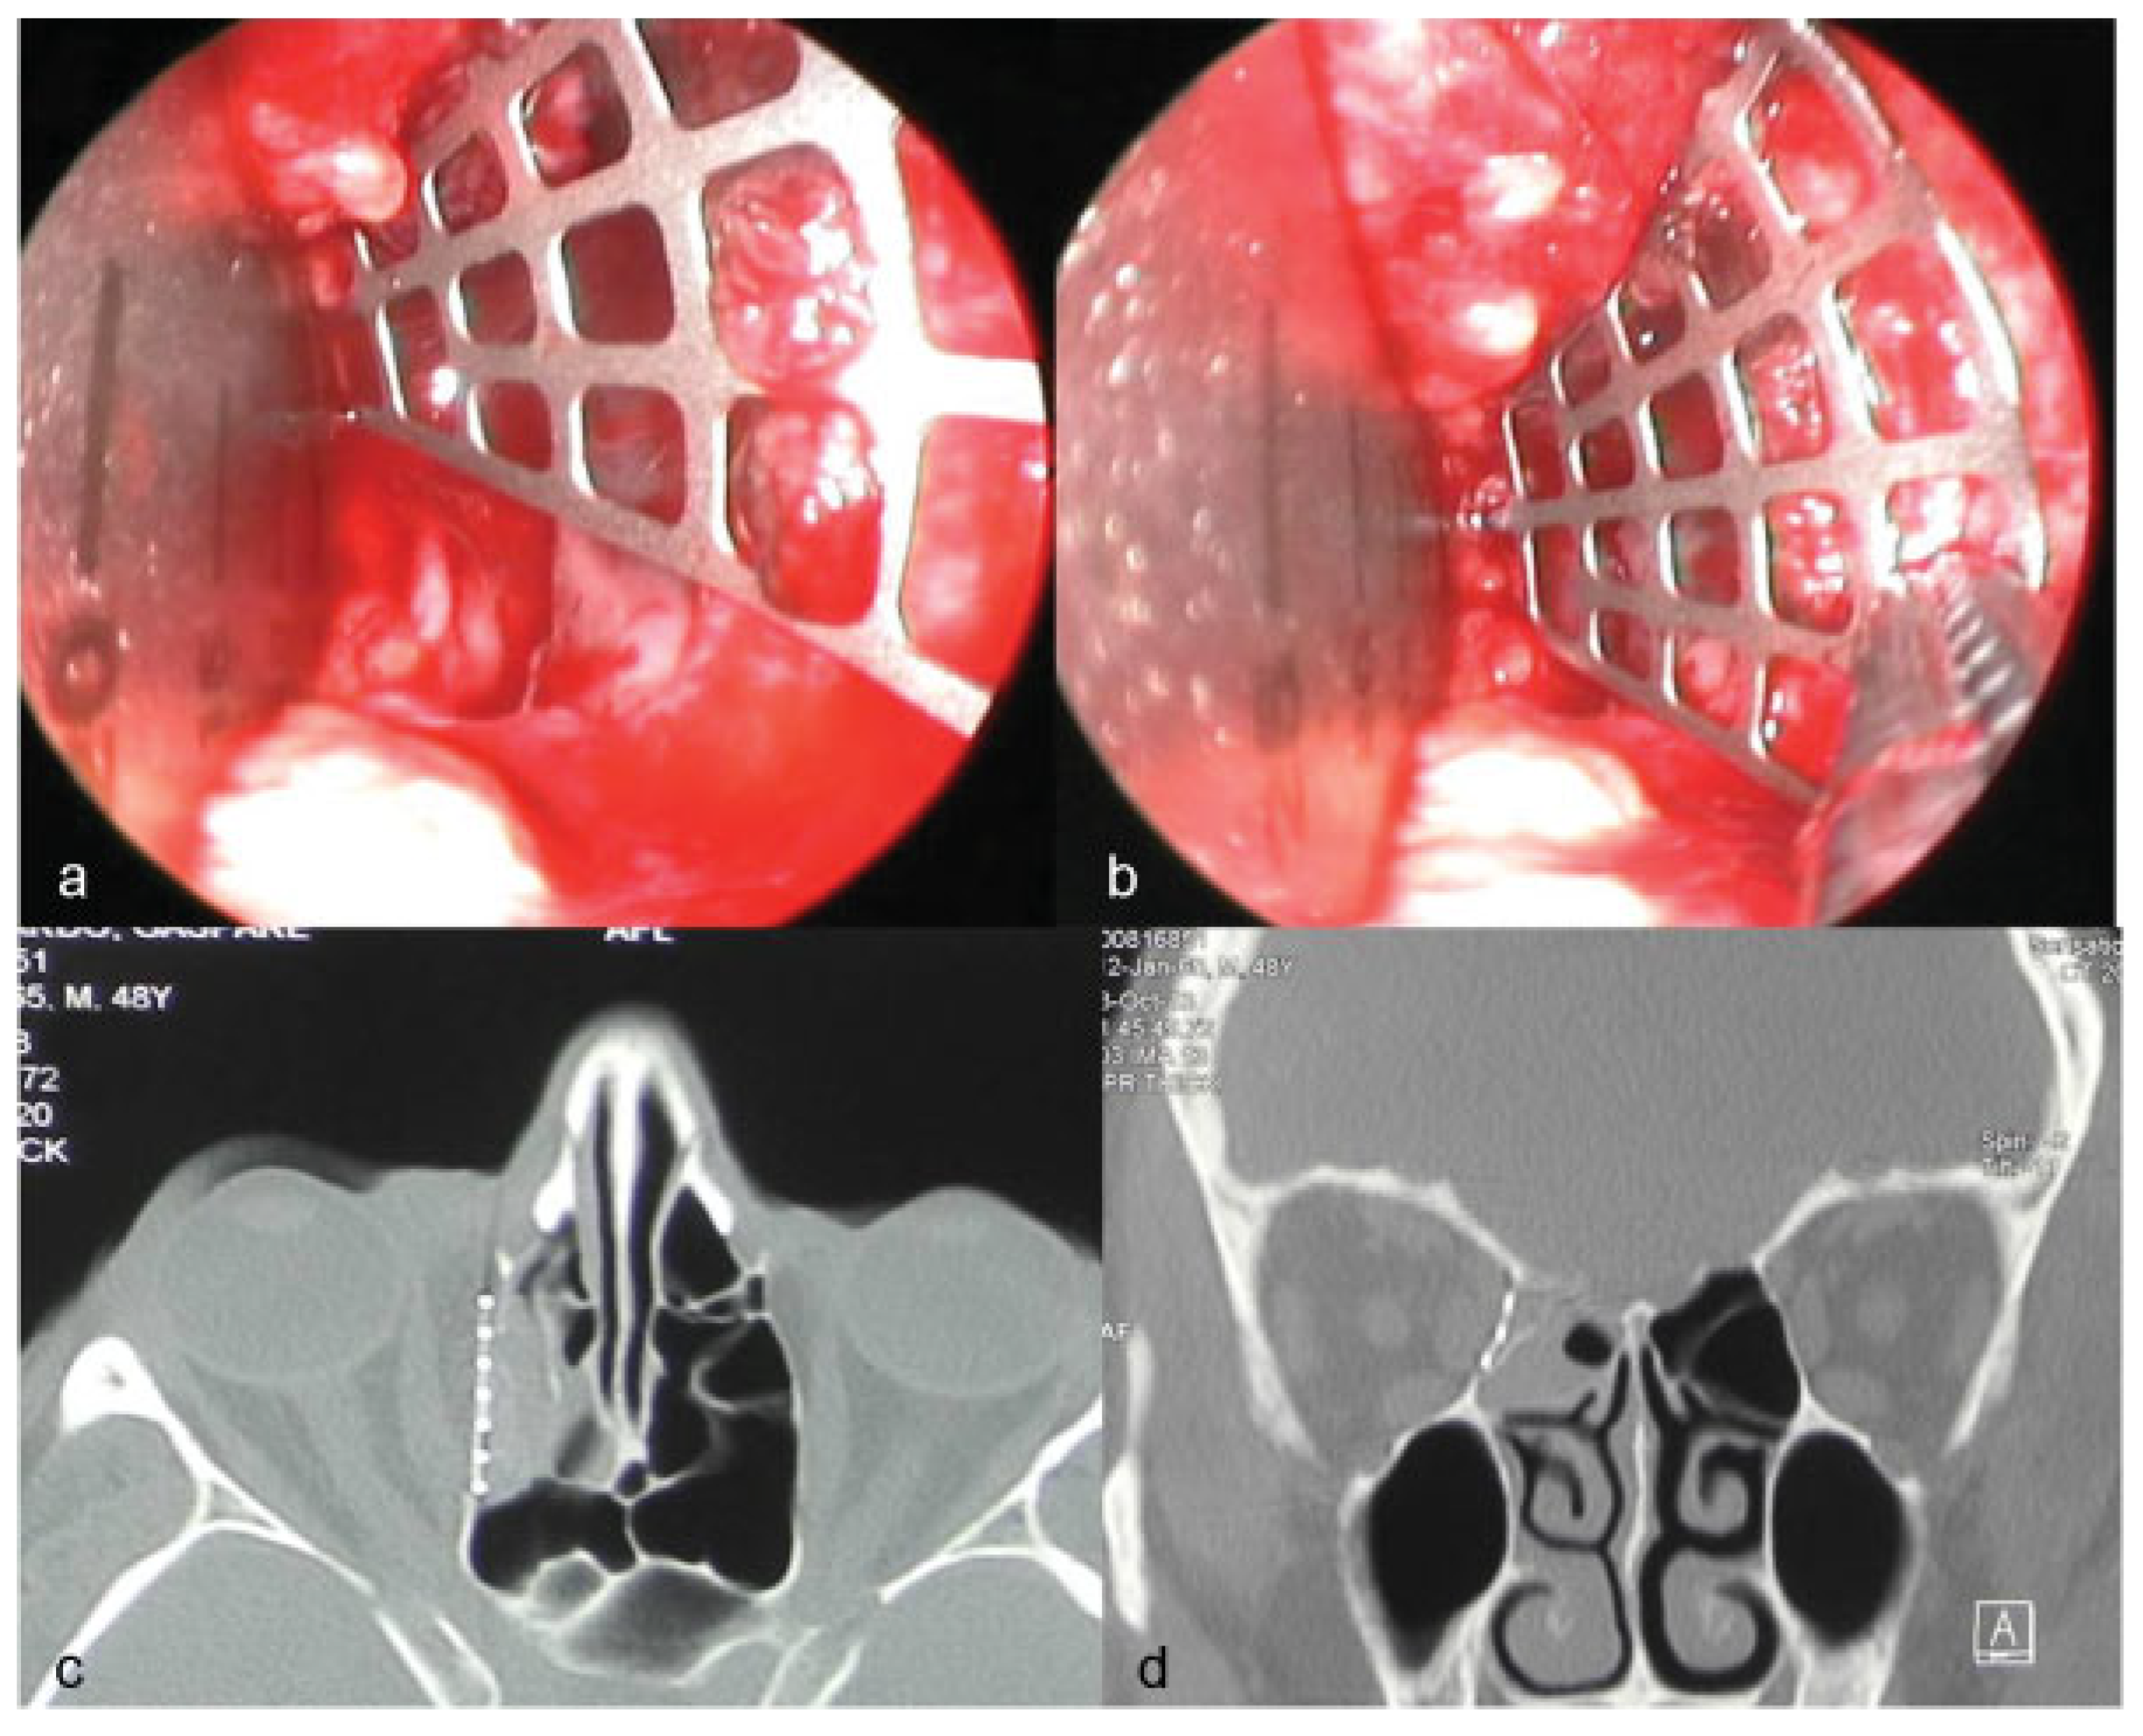

In the group 2 (ENDO) the quality of orbital reconstruction has significantly improved, with the totality of implants correctly placed (Figure 5).

Figure 5. Group 2 (ENDO), endoscope assisted orbital reconstruction in combined medial wall/floor orbital fracture. In this case the quality of orbital reconstruction was rated as satisfactory. (a) Intraoperatory view of prebent anatomical mesh position in respect of the posteromedial ledge of the fracture. (b) Preop CT scan. (c) Postop coronal view. (d) Postop sagittal view.